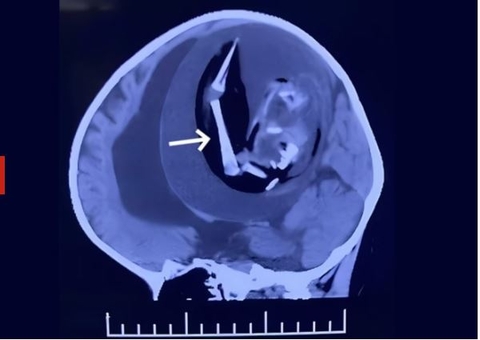

Circula nas redes sociais um vídeo, gravado no dia 17 de junho deste ano, que mostra um objeto voador não identificado (OVNI) em forma de anel nos céus de Valencia, na Venezuela. As imagens, gravadas por volta das 16h54, mostram um círculo escuro flutuando entre nuvens em plena luz do dia.